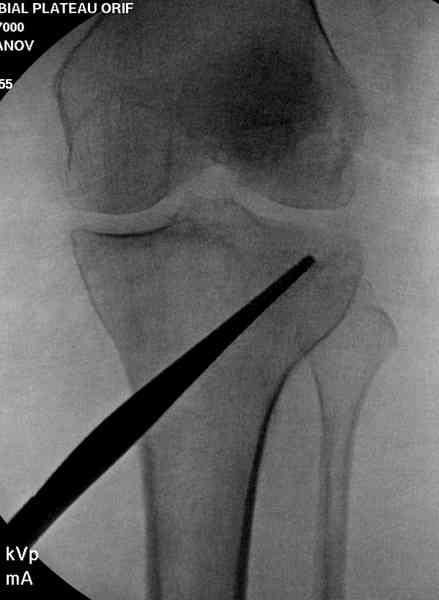

Медиально, обычно на протовоположной

строне, делается окно в кортикальном слое, кривым забойником под рентгеном поднимается импрессия.

Лет 10 назад пытались комбинировать внутрисуставной контроль артроскопом,

но из-за увеличения операционного

времени и сложности манипуляции многие отказались от такой техники.

После заполнения образовавшейся полости в метафизе

кортикальное окно можно прикрыть.